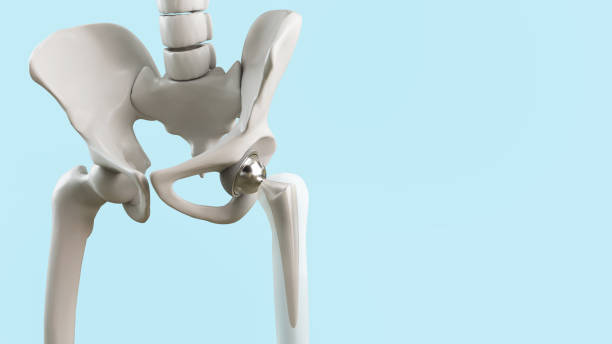

고관절 통증을 관리하고 치료하기 위해서는 다양한 요인을 고려해야 합니다. 통증을 완화하고 원인을 해결하기 위해 개별 환자에게 맞춤형 치료 계획이 필요합니다. 이때, 관절과 근육의 조화로운 기능을 회복시키기 위한 재활운동이 중요합니다.

고관절 통증을 피하기 위해서는 예방이 중요합니다. 특히, 허리와 고관절을 지지하는 근육을 강화하는 운동은 큰 도움이 됩니다. 이러한 운동은 40대부터 시작하여 허리와 관절의 건강을 유지하는 데 도움을 줄 수 있습니다.

이러한 다양한 원인과 치료 방법을 고려하면 고관절 통증을 효과적으로 관리하고 건강한 생활을 유지할 수 있습니다. 통증 원인을 찾아내고 맞춤형 치료를 통해 더 나은 삶의 질을 즐길 수 있을 것입니다.